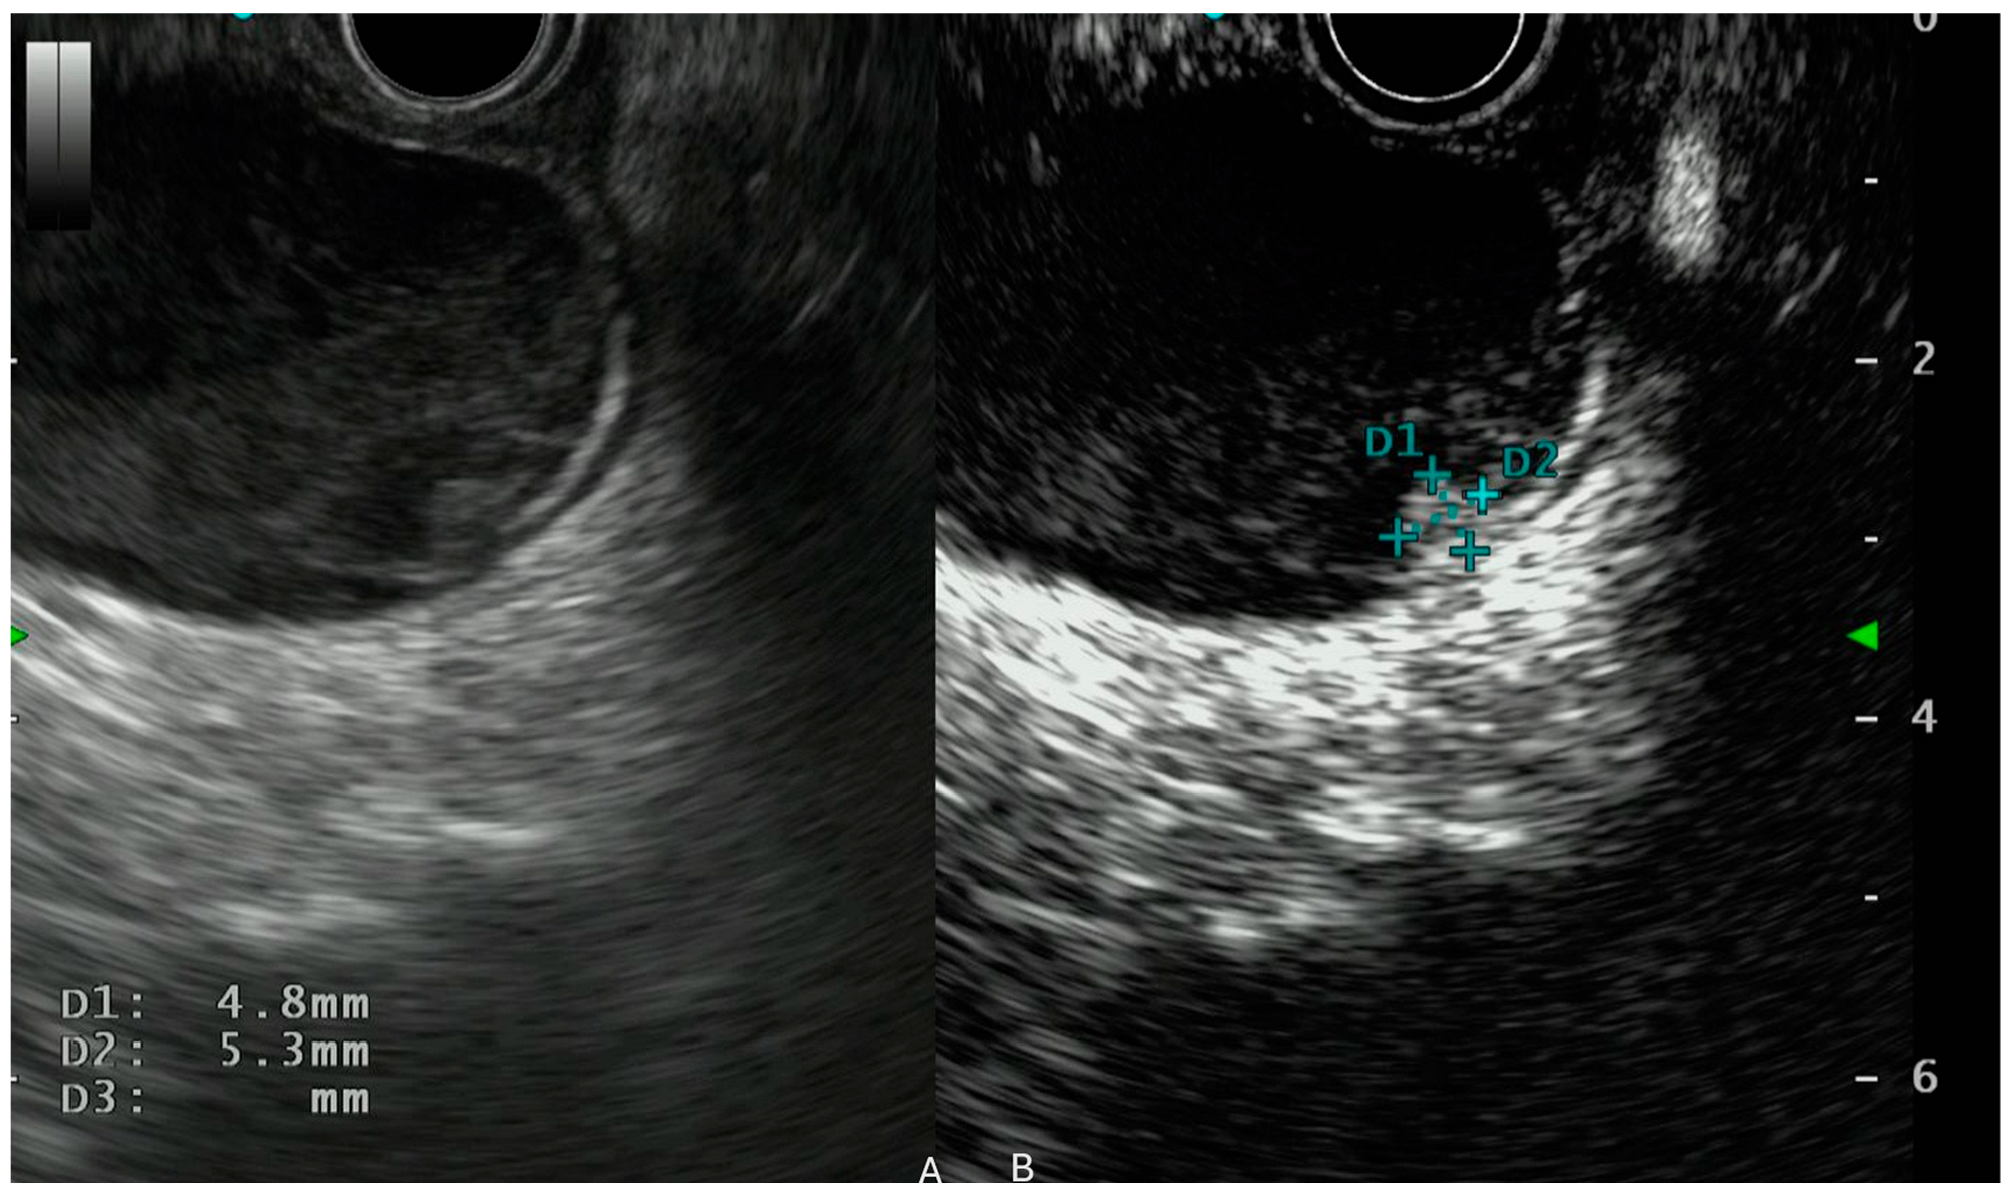

- Iwaya, H.; Hijioka, S.; Mizuno, N.; Kuwahara, T.; Okuno, N.; Tajika, M.; Tanaka, T.; Ishihara, M.; Hirayama, Y.; Onishi, S.; et al. Usefulness of Septal Thickness Measurement on Endoscopic Ultrasound as a Predictor of Malignancy of Branched-Duct and Mixed-Type Intraductal Papillary Mucinous Neoplasm of the Pancreas. Dig. Endosc. 2019, 31, 672–681. [Google Scholar] [CrossRef]

- Ohno, E.; Kawashima, H.; Ishikawa, T.; Iida, T.; Suzuki, H.; Uetsuki, K.; Yashika, J.; Yamada, K.; Yoshikawa, M.; Gibo, N.; et al. Can Contrast-Enhanced Harmonic Endoscopic Ultrasonography Accurately Diagnose Main Pancreatic Duct Involvement in Intraductal Papillary Mucinous Neoplasms? Pancreatology 2020, 20, 887–894. [Google Scholar] [CrossRef] [PubMed]